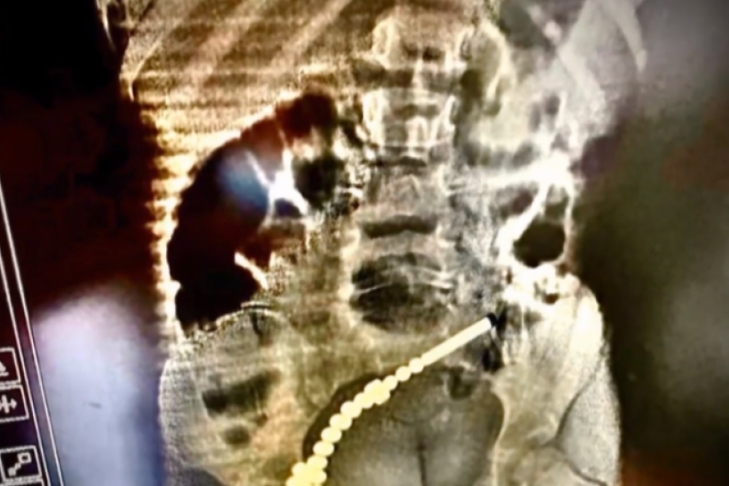

Пробили семь дырок в кишечнике: во Львове популярная игрушка едва не убила двухлетнюю девочку

Во Львове двухлетнюю девочку едва не убила популярная игрушка: ребенок проглотил 31 магнитный шарик из конструктора. Об этом говорится в сюжете "ТСН".

Оказалось, что магниты попали в кишечник, соединились там и пробили семь дырок. Девочку срочно прооперировали.